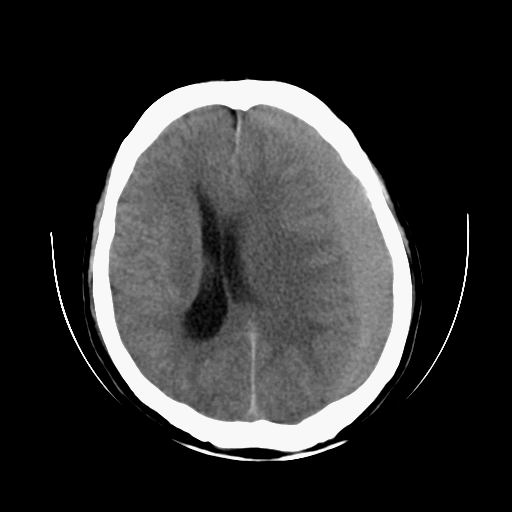

标题: CT13217:头部外伤三月余,头痛三天 [打印本页]

标题: CT13217:头部外伤三月余,头痛三天

左侧慢性硬膜下血肿

太典型,左侧慢性硬膜下血肿

左侧慢性硬膜下血肿,大脑镰下疝。

支持左额颞顶慢性硬膜下血肿伴大脑镰下疝。

血肿是急性、亚急性、还是慢性,要结合外伤时间考虑的,本例头部外伤三个月,应该是明显的慢性硬膜下血肿,但血肿的等密度显然不符合病理改变,估计是合并再次出血,中线结构移位明显,有脑疝形成。应穿刺减压。

血肿是急性、亚急性、还是慢性,要结合外伤时间考虑的,本例头部外伤三个月,应该是明显的慢性硬膜下血肿,但血肿的等密度显然不符合病理改变,估计是合并再次出血,中线结构移位明显,有脑疝形成。应穿刺减压。 大于2个月为慢性出血,2周到二个月为亚急性出血